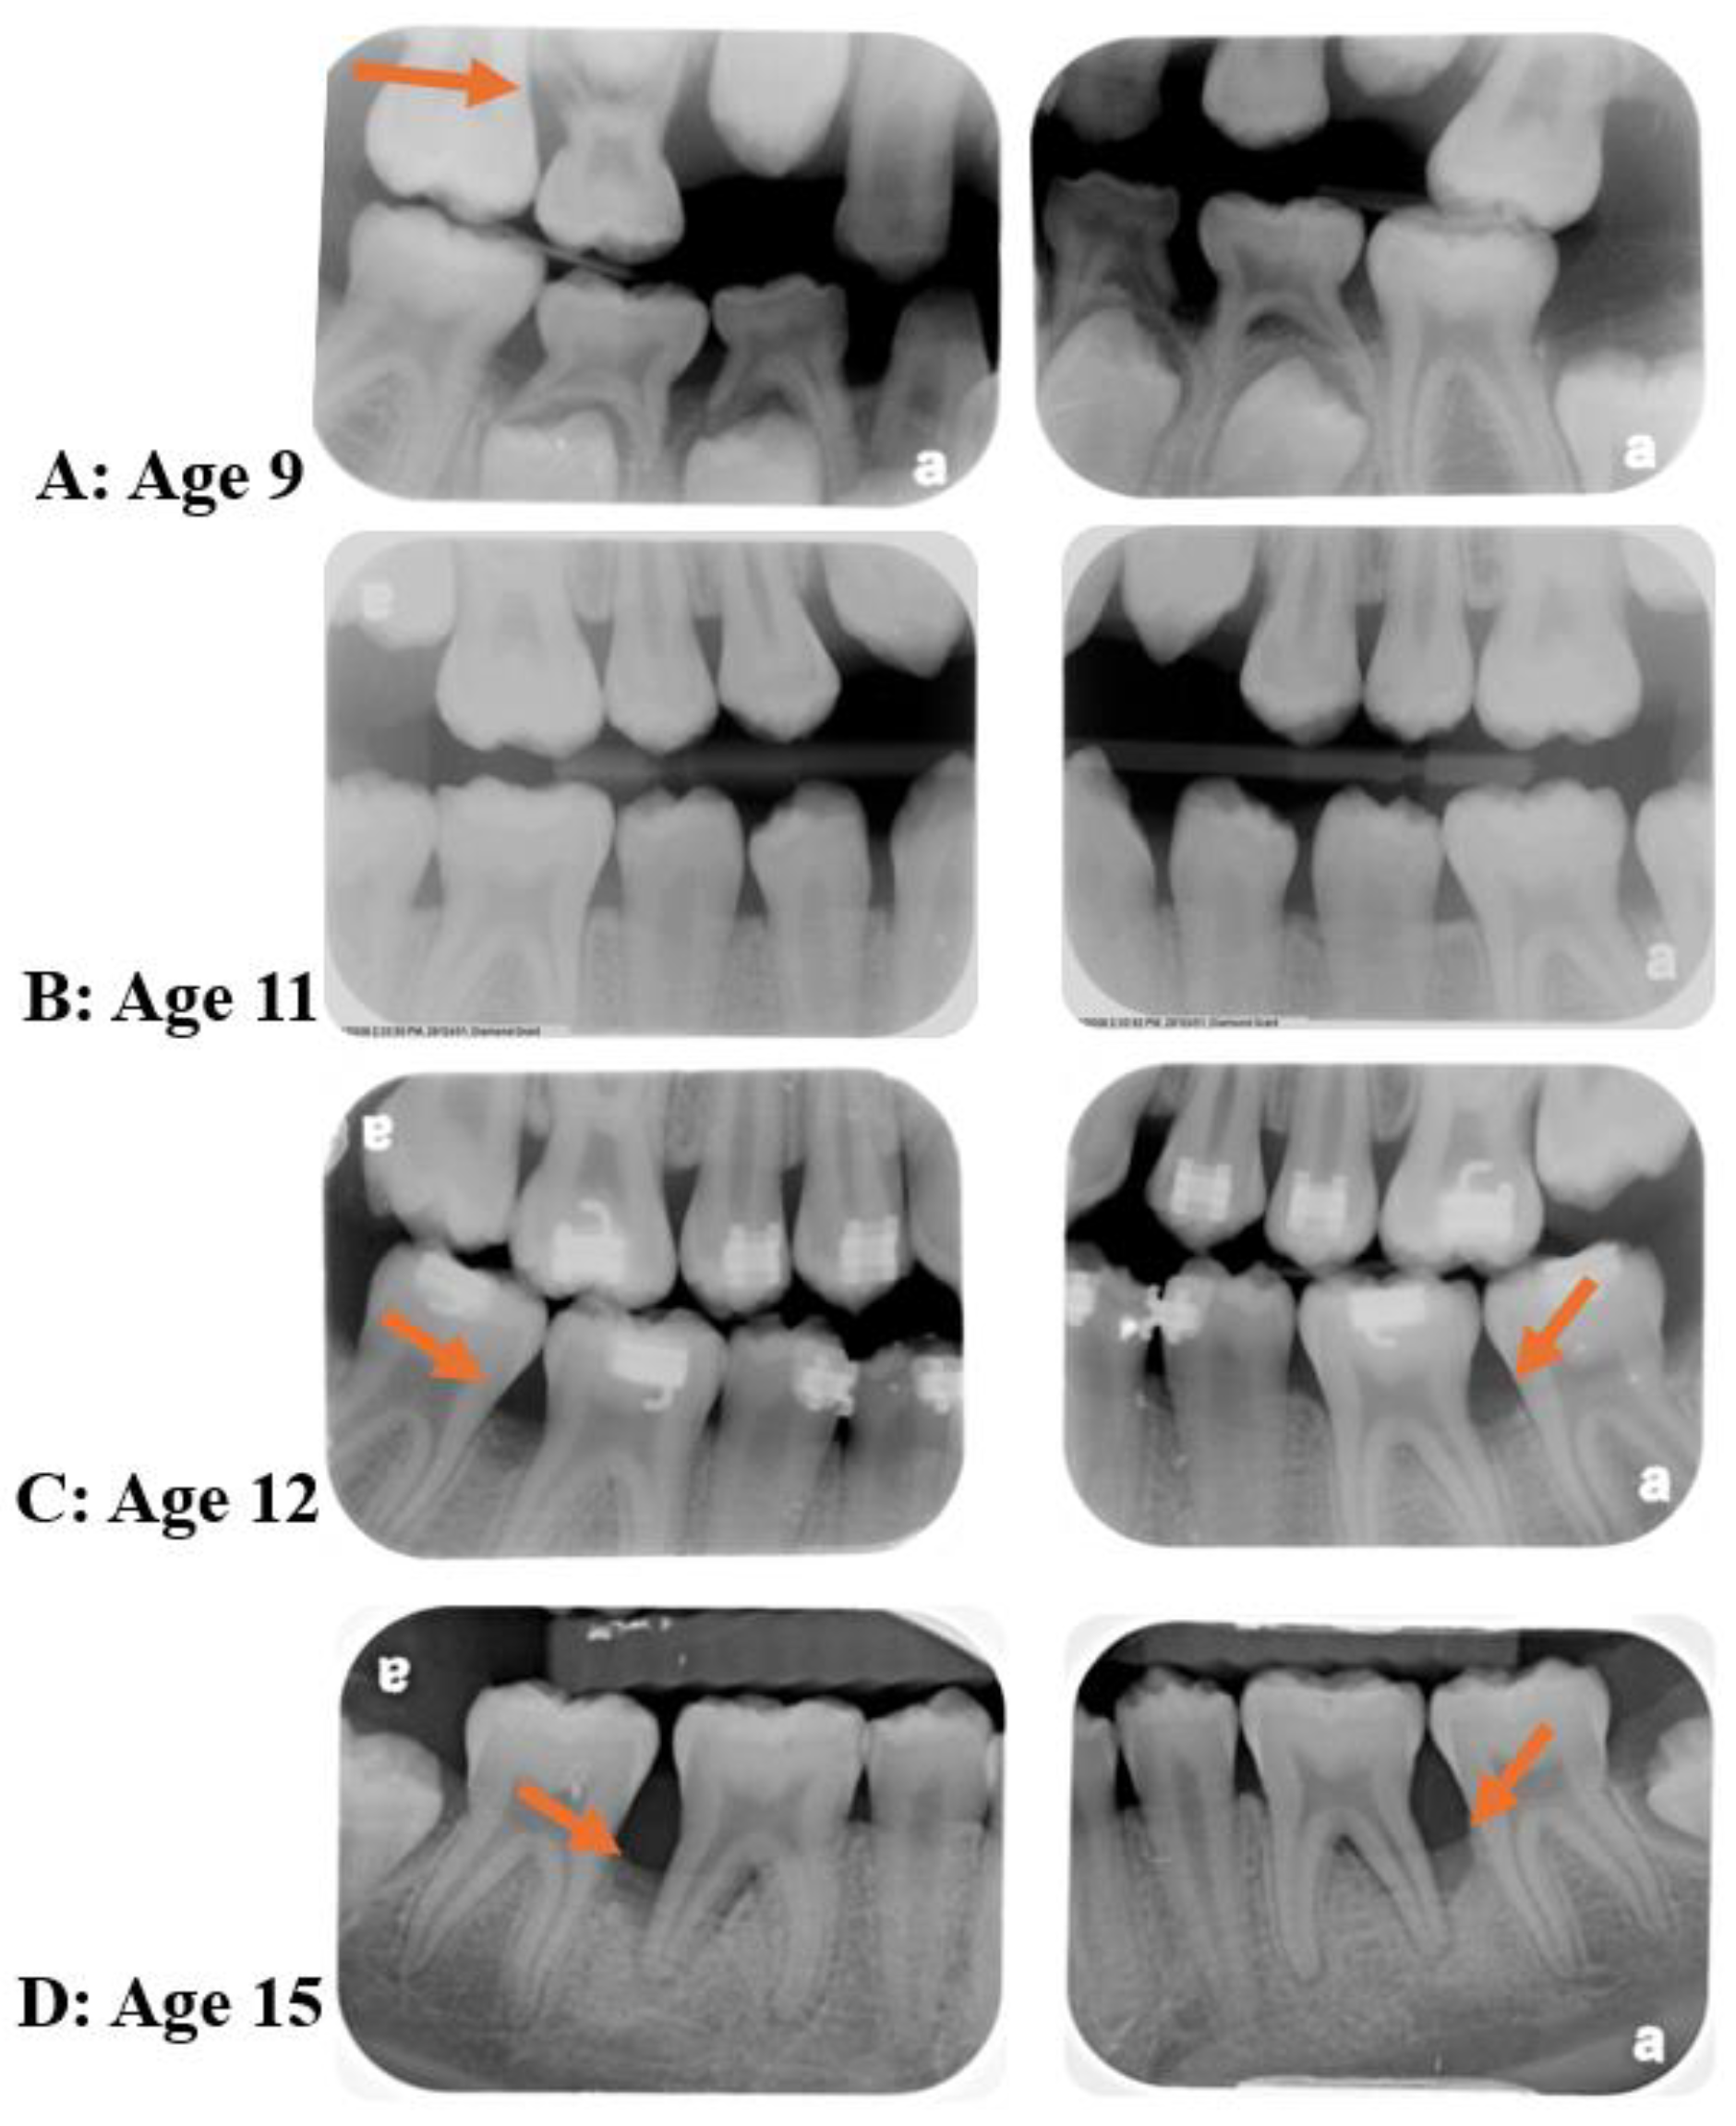

4. Diseases Initial Time-Point

- Merchant, S.N.; Vovk, A.; Kalash, D.; Hovencamp, N.; Aukhil, I.; Harrison, P.; Zapert, E.; Bidwell, J.; Varnado, P.; Shaddox, L.M. Localized Aggressive Periodontitis Treatment Response in Primary and Permanent Dentitions. J. Periodontol. 2014, 85, 1722–1729. [Google Scholar] [CrossRef]

- Miller, K.; Treloar, T.; Guelmann, M.; Rody, W.J.; Shaddox, L.M. Clinical Characteristics of Localized Aggressive Periodontitis in Primary Dentition. J. Clin. Pediatr. Dent. 2018, 42, 95–102. [Google Scholar] [CrossRef]

- Bimstein, E. Radiographic Description of the Distribution of Aggressive Periodontitis in Primary Teeth. J. Clin. Pediatr. Dent. 2018, 42, 91–94. [Google Scholar] [CrossRef] [PubMed]

- Mros, S.T.; Berglundh, T. Aggressive Periodontitis in Children: A 14–19-Year Follow-Up. J. Clin. Periodontol. 2010, 37, 283–287. [Google Scholar] [CrossRef] [PubMed]

- Bimstein, E. Seven-Year Follow-up of 10 Children with Periodontitis. Pediatr. Dent. 2003, 25, 389–396. [Google Scholar]